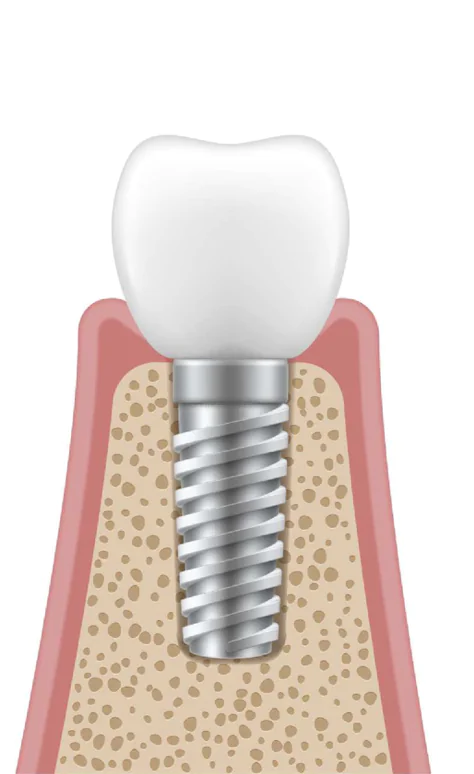

インプラント治療は、歯が失われた箇所に人工の歯の根(人工歯根)を埋め込み、その上に人工歯を被せる治療法です。かつては入れ歯やブリッジが主流でしたが、技術の進歩により、インプラント治療が一般的になりました。

インプラント治療は、歯が失われた箇所に人工の歯の根(人工歯根)を埋め込み、その上に人工歯を被せる治療法です。かつては入れ歯やブリッジが主流でしたが、技術の進歩により、インプラント治療が一般的になりました。

インプラント

インプラントとは、天然の歯と見分けがつかない見た目や咬み心地を実現する先進的な欠損補綴治療法です。この治療は、人工歯根を顎の骨に埋め込んでセラミックの歯を装着することで、天然歯と同等の機能と見た目を実現します。

インプラントとは、天然の歯と見分けがつかない見た目や咬み心地を実現する先進的な欠損補綴治療法です。この治療は、人工歯根を顎の骨に埋め込んでセラミックの歯を装着することで、天然歯と同等の機能と見た目を実現します。